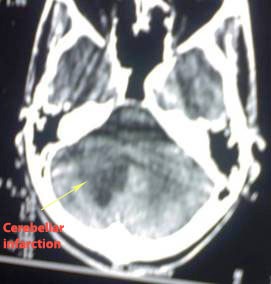

Male patient, in his twenties, drug abuser, presented with acute

unsteadiness.

Examination revealed: Right side gate deviation and right sided

intention kinetic tremors.

CT revealed right cerebellar infarction (arrowed).